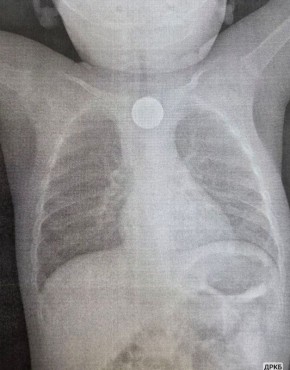

Годовалый малыш проглотил литиевую батарейку и получил химический ожог.

К счастью, врачи ДРКБ смогли вовремя извлечь инородные тела: кроме батарейки малыш проглотил также монету. Ребенок поступил с высокой температурой, рвотой и хрипами при дыхании. Осмотр выявил неизвестное инородное тело, из-за которого ему стало плохо. Малышу провели эндоскопию и извлекли монету и литиевую батарейку, которая вызвала химический ожог слизистой оболочки третьей степени. Сейчас ребенок находится под наблюдением врачей.